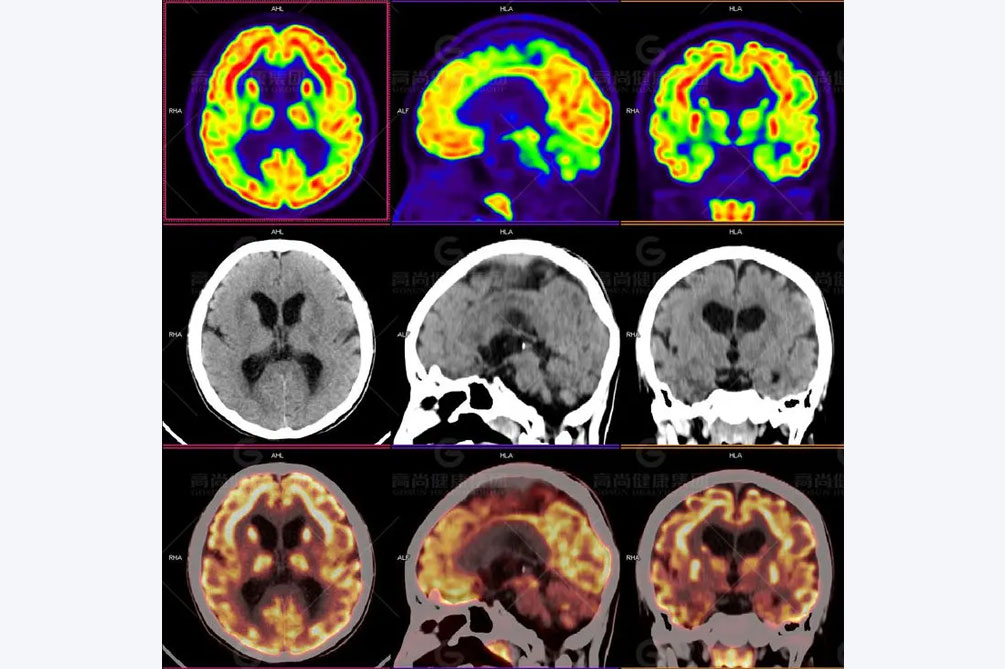

另外,血生化检查要根据年龄和病情做出不同的检查项目。一般包括血钙、血糖、镁、钠、血胆红质、血气分析、血氨、肝功能以及血乳酸等。除此之外,脑脊液检查也是不可少的部分。主要是为了排除颅内的感染以及颅内出血等常见病。影像学检查主要通过CT和MRI检查。CT的应用提高了颅内病变的诊断水平,成为诊断中较为有效的重要手段。非选择性癫痫病人CT检查脑部病变的阳性率。